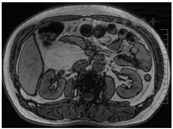

患者男,57岁,因"上腹痛10余d"于2021年12月27日就诊于安徽中医药大学附属芜湖市中医医院专硕研究生培养基地外三科。疼痛呈持续性隐痛,伴后背部胀痛,前倾位疼痛缓解,大便次数增多,每日4次,否认黏液便及血便,近3个月体质量下降约2 kg,既往有高血压、高血脂病史2年余,否认饮酒、吸烟史,否认肿瘤相关疾病家族史。入院体格检查:神志清晰,全身皮肤巩膜无黄染,浅表淋巴结未触及明显肿大,腹平软,肝脾肋下未触及,右上腹部及剑突下深压痛(+),反跳痛(-),右中上腹部可触及一界限不清肿块,质地中等,活动度欠佳。上腹部平扫+增强CT检查提示:肝脏与胰头间腹膜后脂肪源性肿块,胃窦壁稍厚。上腹部上腹部磁共振成像(magnetic resonance imaging,MRI)检查提示:胰头、右肾、下腔静脉之间异常信号包块,T1WI及T2WI呈高信号,抑脂信号减弱,周围组织可见推压征象,考虑脂肪瘤,高分化脂肪肉瘤不除外(图1)。血液癌胚抗原、甲胎蛋白、糖类抗原CA-125、糖类抗原CA-199、总前列腺特异性抗原、游离前列腺特异性抗原等肿瘤标志物检查均在正常参考值范围。血常规、肝肾功能及胰腺内外分泌功能检测等均未见异常。患者于2022年1月10日在全身麻醉下行"腹腔镜腹膜后肿瘤切除术",术中见肝胆胰脾及胃肠道、盆腔无异常,肝下十二指肠右侧接近右肾门处有一大小约9 cm×8 cm×6 cm类圆形包块,有完整包膜,质地中等,肿块内侧与十二指肠及胰头有粘连,有一定活动度,完整游离肿块,处理肿块与胰腺之间粘连,结扎血管,切除肿块,冲洗腹腔,右肝下腹膜后置引流管,关腹。术后予以预防感染、抑酸、抑酶、补液等治疗。术后第1、3、5、8天腹腔引流液分别为470 ml、200 ml、50 ml、20 ml,腹腔引流液淀粉酶分别为14 065 U/L、560 U/L、80 U/L、10 U/L,血淀粉酶分别为1 314.8 U/L、450.0 U/L、112.9 U/L、20.6 U/L,手术切口甲级愈合,术后10 d复查CT提示肝肾隐窝有少量积液,于2022年1月22日带管出院。2022年2月10日门诊随访,一般情况尚可,饮食及二便正常,B超复查未见异常,予以拔管。2022年5月30日门诊随访,患者情况尚好。术后病理检查:大体观灰黄色肿瘤,大小约8 cm×8 cm×6 cm,类圆形,分叶状,包膜完整,包膜周围未见粘连的其他脏器组织,切面质嫩灰黄色,中心部分区域可见少许似海星样灰白色纤维样组织。镜下检查见肿瘤表面为完整的纤维性包膜,肿瘤组织主要由大量成熟的脂肪组织、纤维结缔组织、大小不等的厚壁和薄壁血管、少量成熟的淋巴组织、周围神经组织组成,其内混杂的纤维结缔组织中可见形态良好的腺泡细胞和导管,细胞无异型性(图2)。免疫组化检查结果示管状腺体CK7(+),CK20(-), CDX2(+),SMAD4(+),腺泡细胞trypsin(+),syn(-)。S-100脂肪细胞(+),梭形细胞少许(+),CD34脂肪细胞(+),血管内皮(+),Vim梭形细胞(+),脂肪细胞(+),平滑肌肌动蛋白(-),肌细胞生成素(-),B淋巴细胞瘤-2基因少许梭形细胞,CD10部分脂肪细胞、梭形细胞(+),细胞增殖抗原标记物(-),增殖细胞核抗原腺上皮(+),淋巴细胞(+),脂肪细胞梭形细胞(少许+),Des部分梭形细胞,CK7(-),CK5腺泡、导管上皮(+)。病理诊断:腹膜后胰腺错构瘤(pancreatic hamartoma,PH)。患者术后有少量胰漏发生,经通畅引流治愈,术后随访6个月情况良好。

注:MRI为磁共振成像